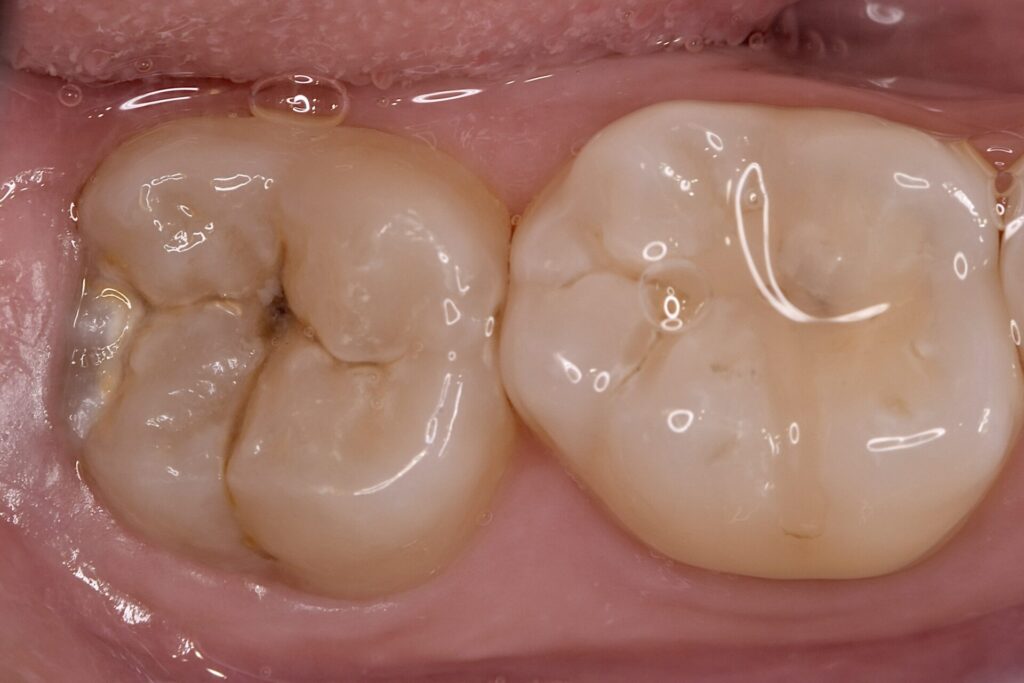

40代 虫歯治療 ダイレクトボンディング #52

Before

After

| 年齢 | 40代 | 治療方法 | ダイレクトボンディング |

| 性別 | 男性 | 通院回数 | 2回 |

| 主訴 | むし歯を治したい | 費用 | 115,500円(税込) |

| 治療のメリット | 歯を削る量を少なくできる・自然な見た目・境目がピッタリできる | ||

| 治療のデメリット | 大きい虫歯治療には適応できない場合がある | ||